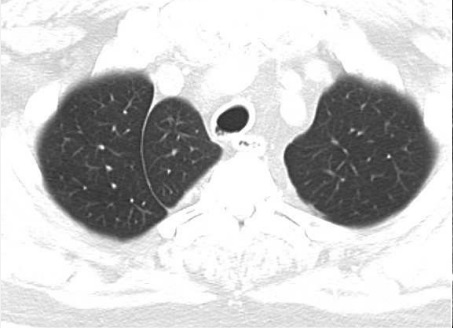

Image radiologique TDM d'une pleuresie du

poumon droit de moyen abondance . La liquide

transudat ou exsudative declive au sinus costo

diaphragmatique lateral et posterieur du poumon

droit en formant de aspect de masse non systematisee

, isopdensite , homogene . Image radiologique

TDM en coupe axiale et coronal , fenetre

mediastinale et image radiologique TDM coronal ,

fenetre parenchymateuse |